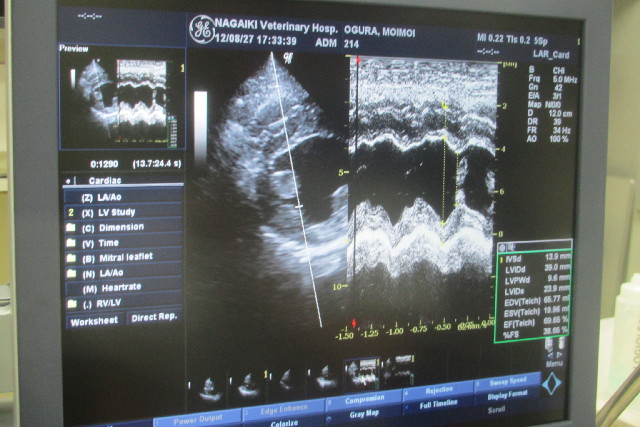

夏バテ気味なのだとは思うのですが、もいちゃんすごく疲れやすいし、覇気がないし、すぐにハアハアしちゃうし、前回のレントゲンで心臓が寝ているっていわれちゃったし、念のため心臓のエコーしてもらいました。

今回は便の動きや、心臓が正しく収縮できているか比率をみてくれました。

38.65%で大丈夫とのことです(o^-')b グッ!

もいちゃんの心臓の筋肉さんはちゃんとした厚さで動きで元気に動いてくれていました♪

弁の動きもよ〜くわかりましたヨ!(^^)!